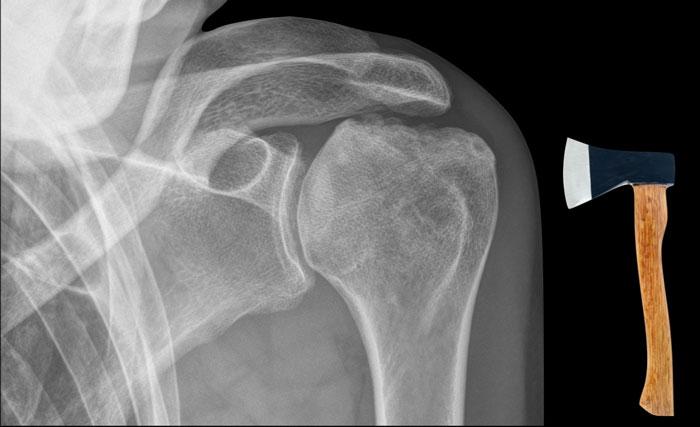

A. Vôi hóa mô mềm tại chóp xoay. Bệnh nhân được tiêm dưới mỏm cùng vai để giảm triệu chứng.

B. Sau tiêm corticosteroid, xuất hiện mất sụn khớp nặng tại khớp ổ chảo-cánh tay và phá hủy xương đầu trên xương cánh tay. Đây là hậu quả của viêm khớp nhiễm khuẩn, một biến chứng hiếm gặp của tiêm khớp.

Dấu hiệu rìu so với hoại tử vô mạch

Dấu hiệu rìu khác với biến dạng thấy trong hoại tử vô mạch, trong đó có hiện tượng xẹp tiến triển của bề mặt khớp chỏm xương cánh tay.

Vai Milwaukee

Hội chứng vai Milwaukee là một bệnh lý khớp vai hiếm gặp có thể bắt chước hình ảnh vai hình rìu.

Bệnh đặc trưng bởi đứt gân chóp xoay, tràn dịch khớp và bao hoạt dịch lớn kèm lắng đọng tinh thể hydroxyapatite dẫn đến phá hủy nhanh chóng khớp ổ chảo-cánh tay.

Hình ảnh

Phá hủy nặng nề chỏm xương cánh tay với di lệch lên trên và bào mòn mỏm cùng vai, cho thấy đứt hoàn toàn gân chóp xoay.

Trong hội chứng vai Milwaukee, triệu chứng lâm sàng thường nhẹ hơn nhiều so với mức độ tổn thương trên hình ảnh.

Trong trường hợp này, không có nỗ lực chẩn đoán tinh thể canxi hydroxyapatite trong màng hoạt dịch.

Dựa trên các dấu hiệu lâm sàng và X-quang, hội chứng vai Milwaukee đã được chẩn đoán.